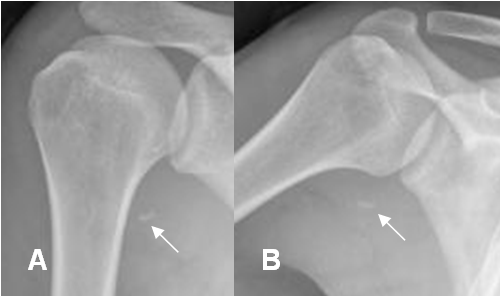

Fig 78 B. Lesión BHGLA.

A: Rx AP y B: Rx axial. Fragmento óseo en la parte interna del brazo, que corresponde a avulsión, por ruptura del ligamento glenohumeral inferior.